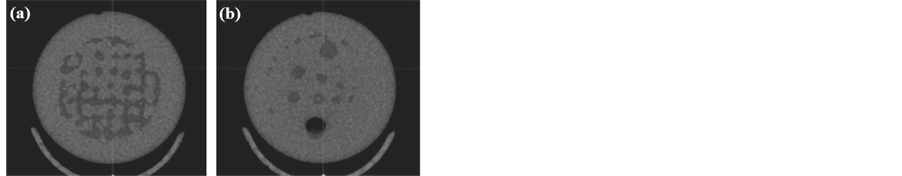

The micro-CT images are obtained through transversal acquisitions at the levels of the homogeneous region of the proposed phantom and patterns number 2, 4, 5, 6 and 7 (Figure 2). They concerned uniformity (Figure 5(a)), spatial linearity (Figure 5(b)), Hounsfield unit linearity (Figure 5(c)), low contrast detectability (Figure 5(d)), diffusion profile (Figure 5(e)) and slice thickness (Figure 5(f)).

The micro-SPECT images are obtained through transversal acquisitions at the levels of the homogeneous region of the proposed phantom and patterns number 2 and 3 (Figure 2). They concerned uniformity (Figure 7(a)), spatial resolution (Figure 7(b)) and spatial linearity (Figure 7(c)).

Micro-SPECT/CT acquisitions are made following the micro-CT acquisitions. Indeed, it comes to be positioned on the micro-CT acquisitions for achieving the micro-SPECT acquisitions, and then we proceed with image fusions of the two modalities for each slice. This operation concerned acquisitions made at the level of patterns number 2 and 3. Thus, we are able to test micro-SPECT/CT image of spatial linearity (Figure 8(a)) and spatial resolution (Figure 8(b)).

For the micro-SPECT unit, it was found that the spatial resolution is close to 1mm as it was possible to distinguish a boundary separation between the images of the two holes of 1mm diameter and separated by a distance also of 1 mm (Figure 7(b)). In addition, the spatial linearity test reveals the presence of geometric distortions in the middle region of the useful field of view (Figure 7(c)) was remarked. So, it is necessary to do spatial linearity correction of the micro-SPECT system detector.

For the micro-CT acquisitions, the spatial linearity of this unit was tested (Figure 5(b)) and the diffusion profile was easy to measure on Figure 5(e) using Equation (4). As for uniformity, it was still easy to calculate on Figure 5(a). While the Hounsfield units of Figure 5(c) were clearly measurable for air, Teflon and polyethylene, they were not in the case of water because of the presence of the contrast agent (Iomeron 400). The same for the low contrast detectability (Figure 5(d)), because the Iomeron 400 increased shift of X-ray attenuation rate between the Plexiglas and the solution, which makes the condition of low water-Plexiglas contrast (Figure 9) no longer there. So, it is convenient to work without any contrast agent. Moreover, to measure slice thickness, low contrast with water gives more uncertain results (Figure 9). Thus, the results in this side are better with the contrast agents (Figure 5(f)).

For micro-SPECT/CT acquisitions (fusion), it was noticed that the global uniformity parameter is rather imposed by micro-SPECT unit which presents weaker qualities compared to micro-CT unit. The same applies to geometric distortions; they are more pronounced in Figure 8(a). For spatial resolution of the whole system, it is better than 1 mm because the fusion with micro-CT can improve this quality. These constitute the advantages of multimodal imaging systems (micro-SPECT and micro-CT).